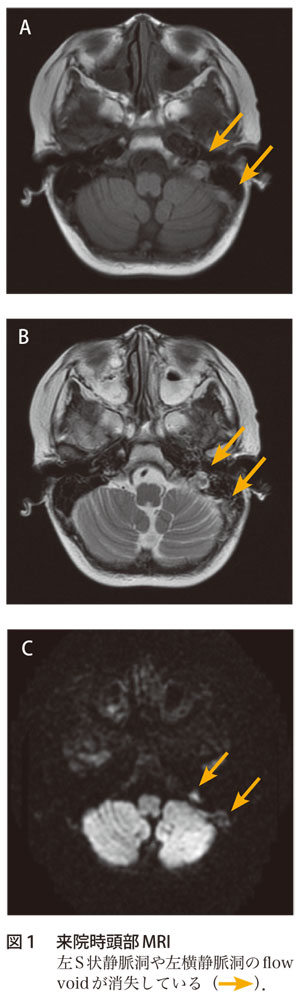

て,右内頸動脈海綿静脈洞瘻が疑われ同日緊急入院 となった。 初診時所見:意識清明で体温3 度であった。 視力は右05 左09 と右視力低下を認めた。右眼球 突出,右上眼瞼発赤・腫脹を認め(図1),開眼は 臨床 副鼻腔炎に続発した海綿静脈洞血栓症の1 例る深部の静脈洞血栓になりまして、こ の場合は意識障害が進行することもあ ります。 齊藤 視力障害などもあるのですか。 伊澤 海綿静脈洞血栓症の場合は目 の痛み、眼球突出、眼瞼浮腫、眼球運 動障害、このようなものも出てきます副鼻腔炎から海綿静脈洞血栓症,髄膜炎を併発し急激に失明に至った1症例 Loss of vision in a case of sinusitis with secondary cavernous sinus thrombosis and meningitis 小嶌 美恵子 1, 兜坂 法文 1, 和田 公平 2, 深尾 篤嗣 3 Mieko Kojima 1, Norifumi Tosaka 1, Kouhei Wada 2, Atsusi Fukao 3 1

右海綿静脈洞から蝶形頭頂静脈洞,一部眼窩にかけて高信号域を認めた. 表1 有痛性眼筋麻痺の原因疾患3)一部改変 血管障害 脳出血,くも膜下出血,下垂体卒中,脳動脈瘤,糖尿病性眼筋麻痺 (痛みは稀),ccf,海綿静脈洞血栓症化膿性海綿静脈洞血栓症,細菌性髄膜炎を来たしたLemierre症候群 52:7 Fig 1 Eye movement of the patient His right eye showed slight exophthalmos and swelling of the eyelid Lateral and inferior gaze of his right eye movement was disturbed Fig 2内科学 第10版 脳静脈洞血栓症・脳静脈血栓症の用語解説 概念 脳静脈洞が種々の原因による血栓で閉塞され頭痛などの脳圧亢進症状をきたすもので,血栓が静脈洞から脳表静脈に及ぶと脳局所症状を呈する.病変は脳静脈洞の血栓性閉塞が主体であるが,脳表静脈に血栓が進展した場合には